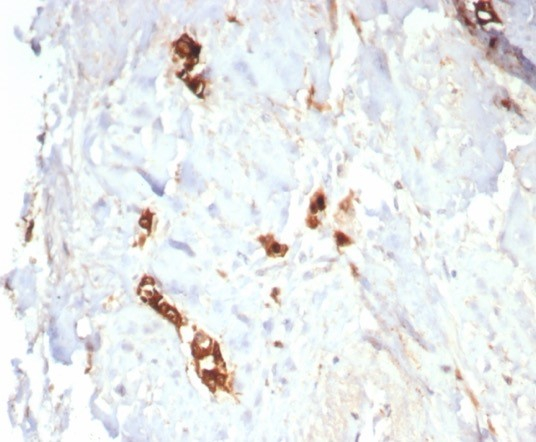

Formalin-fixed, paraffin-embedded human lactating breast stained with Mammaglobin A antibody (MGB/7980R). HIER: Tris/EDTA, pH9.0, 45min. Secondary: HRP-polymer, 30min. DAB, 5min.